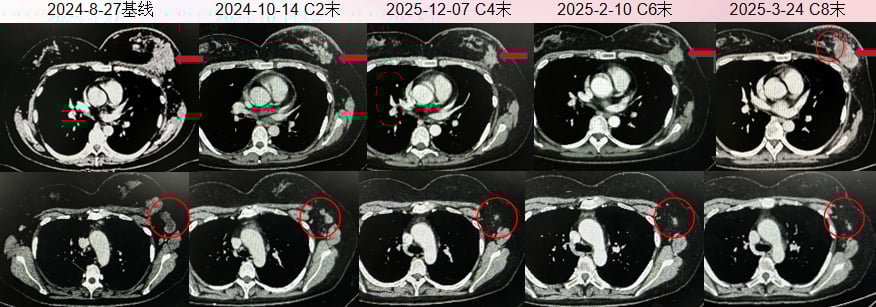

医疗团队迅速制定了一线治疗方案(THPy方案):白蛋白紫杉醇 + 曲妥珠单抗 + 吡咯替尼,并辅以地舒单抗治疗骨转移。然而,该方案并未能有效控制病情。仅仅治疗了2个周期(约1个半月),患者的头颅病灶便出现进展,整体疗效评估为疾病进展(PD)。

面对一线治疗的失败和脑转移的严峻挑战,医生团队果断调整为二线治疗方案。自2024年9月起,患者开始接受德曲妥珠单抗(Enhertu, T-DXd)治疗,并针对颅内病灶联合了射波刀及全脑放疗。像德曲妥珠单抗这样的前沿靶向药,为许多患者带来了新的希望。如果您想了解该药物的详细信息,包括其价格和购买渠道,可以访问MedFind靶向药代购平台。

这一次,治疗效果令人振奋:

- 头颅病灶:经过8个周期的治疗,MRI复查显示颅内转移瘤明显缩小。

- 乳房及淋巴结:原发灶及肿大淋巴结均显著缩小。

- 骨转移:骨病灶保持稳定,并出现部分成骨性改变,提示病情得到控制。

整体疗效评估为部分缓解(PR),德曲妥珠单抗展现了其在经治HER2阳性晚期乳腺癌,尤其是伴有脑转移患者中的强大疗效。